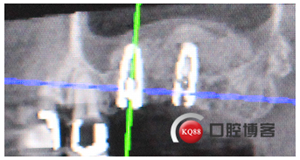

再看看片子。

問題在這里,不給留位置怎么會有齦乳頭,沒有間隙怎么清潔?這完全是技工的錯吧?算了我自己修整一下吧。

再看看是不是效果好多了?哼!我就是個較真兒的人。